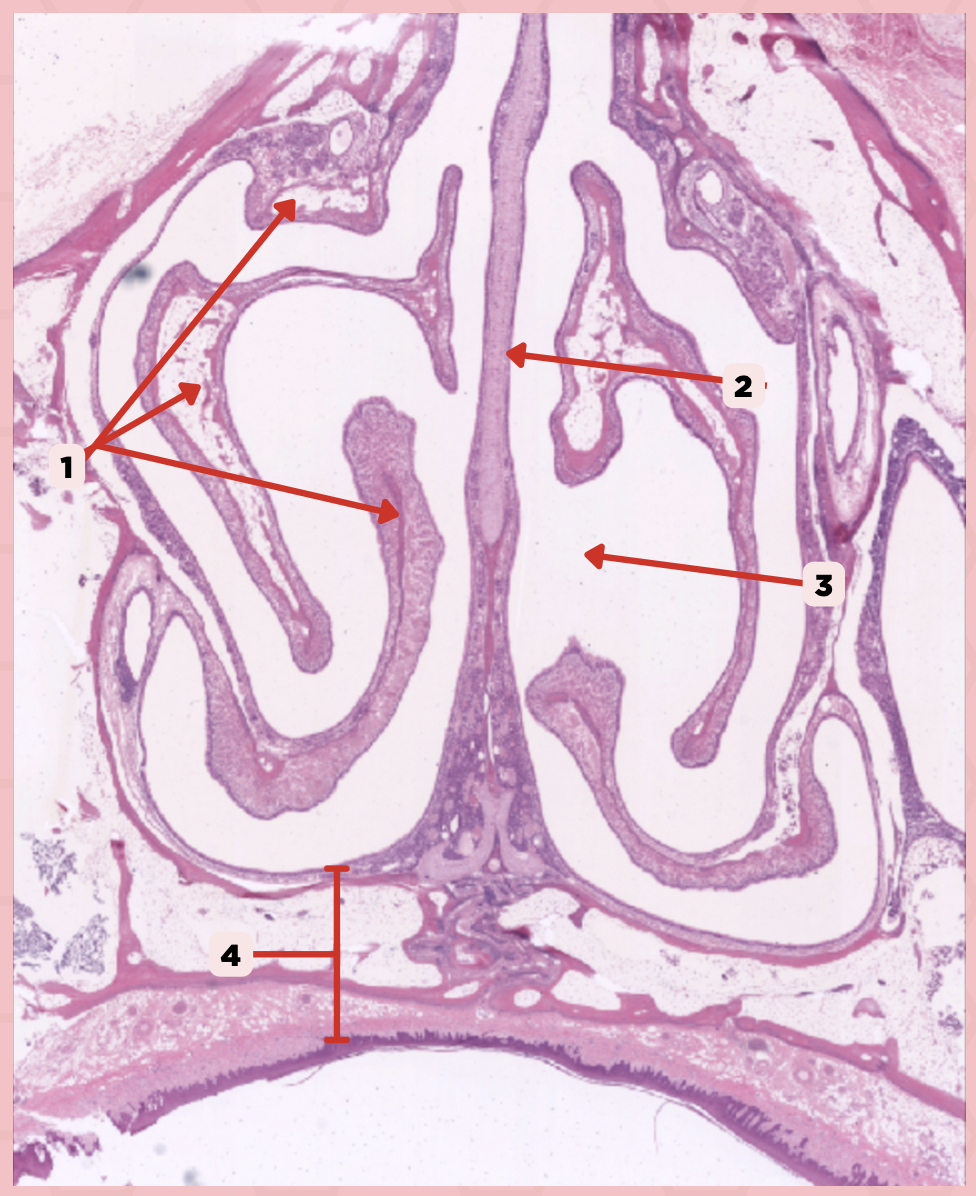

What type of cells make up #1?

Lamina Propria

Identify the structure labeled as 1.

Hyaline Cartilage

Identify the structure labeled as 2.

Respiratory Epithelium

Identify the structure labeled as 3.

Nasal Cavity

Identify the structure labeled as 4.

Basal Cells

Identify the structure labeled as 5.

Goblet Cells

Identify the structure labeled as 6.

Ciliated Columnar Cells

Identify the structure labeled as 7.

Adipose tissue

What type of tissue is sometimes seen between the bony spicules?

Serous and Mucous Glands

What glands are present in the Lamina Propria?